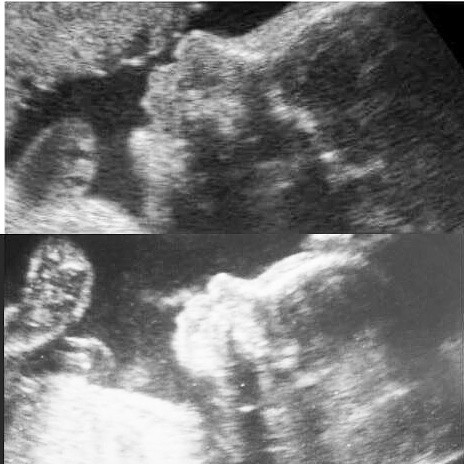

24 неделя,изменения, 2 сосуда в пуповине

Вчера были на доплере, наш малыш ну прям точная копия братика))))

Для сравнения, наверху Геворг, внизу Давид))))

всегда хотела двойняшек, видимо сыновья у меня будут очень похожи)